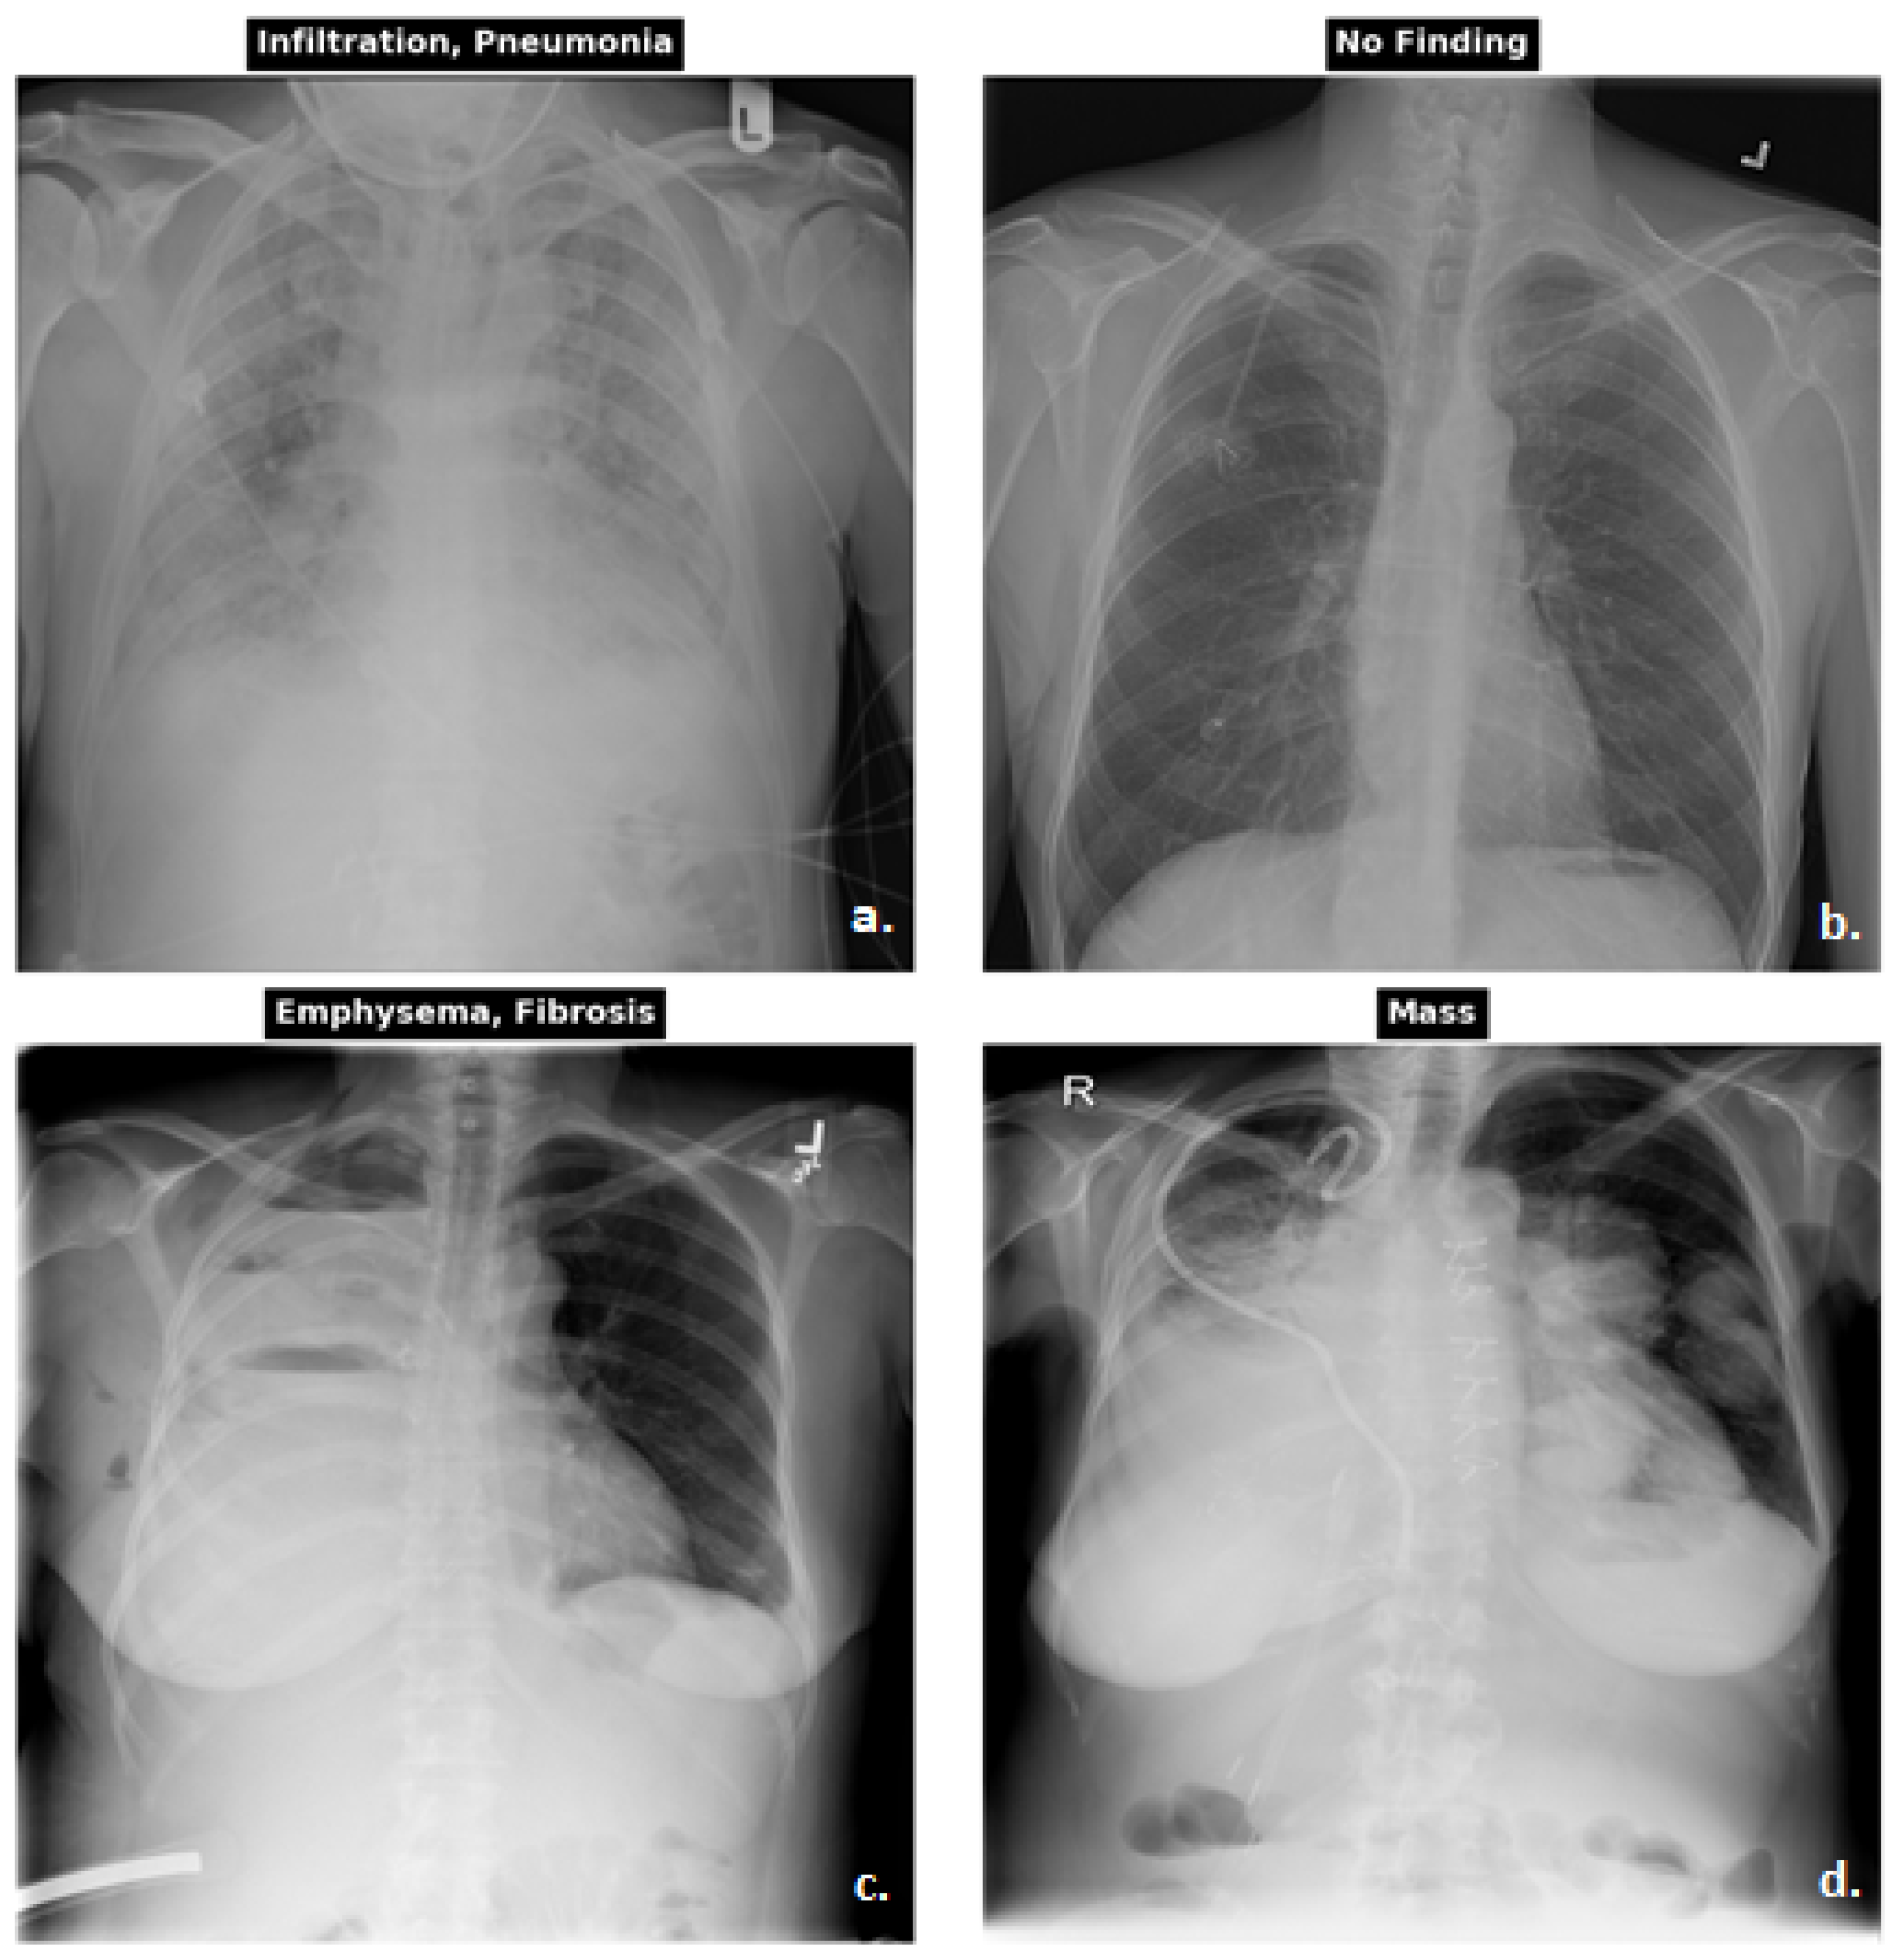

3.1.1. Dataset

- Wang, X.; Peng, Y.; Lu, L.; Lu, Z.; Bagheri, M.; Summers, R.M. Chestx-Ray8: Hospital-scale chest X-ray database and benchmarks on weakly-supervised classification and localization of common thorax diseases. In Proceedings of the 2017 IEEE Conference on Computer Vision and Pattern Recognition (CVPR), Honolulu, HI, USA, 21–26 July 2017; pp. 3462–3471. [Google Scholar] [CrossRef]

- CXR-PadChest. Available online: https://bimcv.cipf.es/bimcv-projects/padchest (accessed on 24 May 2025).

- Kermany, D.S.; Goldbaum, M.; Cai, W.; Valentim, C.C.S.; Liang, H.; Baxter, S.L.; McKeown, A.; Yang, G.; Wu, X.; Yan, F.; et al. Identifying medical diagnoses and treatable diseases by image-based Deep Learning. Cell 2018, 172, 1122–1131.e9. [Google Scholar] [CrossRef] [PubMed]